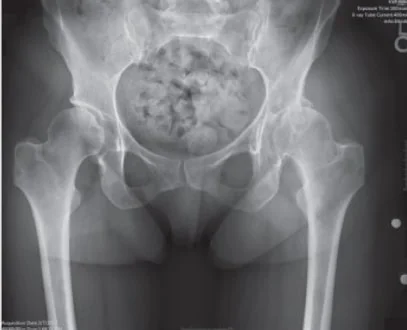

1. Avascular Necrosis:

Results from disruption of blood supply of femoral head. Lack of blood supply causes death of bone tissues, collapse of bone & ultimately secondary osteoarthritis of the hip.

Common causes are:

• Alcohol abuse & smoking

• Steroid abuse

• Post traumatic (Neck femur fracture/hip dislocation)

• Idiopathic

• Post Covid AVN

• Sickle cell anemia/Gaucher's disease